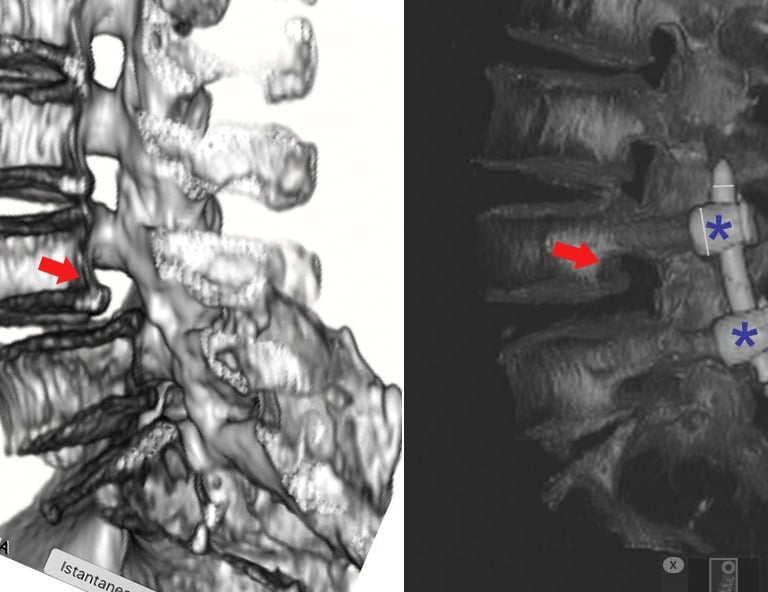

La spondilolisi è una frattura da stress dell’istmo vertebrale, una piccola porzione dell’arco osseo posteriore della vertebra. Si tratta di una condizione subdola perché spesso asintomatica, ma che può evolvere in spondilolistesi, una problematica più seria caratterizzata dallo scivolamento vertebrale.

Diagnosi: RX e Risonanza Magnetica per una Conferma Certa

RX in proiezione obliqua: utile per identificare il tipico “Doggy’s Collar Sign”.

Risonanza Magnetica (RMN): permette di evidenziare le fasi iniziali della patologia con maggiore precisione.